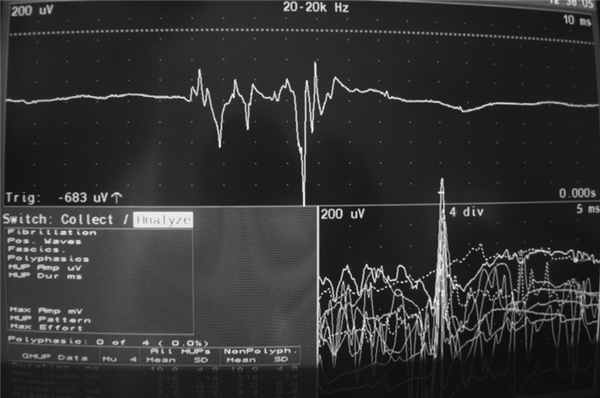

При электроэнцефалографии патологии выявлено не было. Во время непроизвольных сокращений мышц левой руки патологических изменений на ЭЭГ не регистрировалось. Игольчатая электромиограмма (ЭМГ) выявила разряды из нескольких двигательных единиц m. extensor dig. com. слева (сегмент С7), продолжительность разряда 70 мс и амплитуда 1400 мкВ. При проведении исследования в других мышцах, иннервируемых другими сегментами, ответы не были получены (рис. 3). Рисунок 3. Игольчатая ЭМГ. Разряд с m. extensor dig. сom. продолжительностью 70 мс и амплитудой 1400 мкВ (в других мышцах из других сегментов ответы не были получены). При стимуляционной ЭМГ было выявлено нарушение проведения по моторным волокнам левой руки на уровне локтя (туннельный синдром), по нервам левой руки изменений обнаружено не было.

Поверхностная ЭМГ при СМ позволяет выявить ритмичные или полуритмичные разряды, которые обычно синхронны, со стереотипной продолжительностью и частотой. ЭМГ-исследование при ССМ демонстрирует разряды продолжительностью более 100 мс (до 1000 мс) и ограниченные одним или двумя соседними миотомами. При ПСМ миоклонические разряды могут длиться от 50 мс до 4 с, формируются они из абдоминальных и шейных сегментов и распространяются медленно рострально и каудально, при этом краниальные мышцы остаются интактными. Для ПСМ характерны задержка между разрядами и последовательное их распространение, что обусловлено медленным проведением импульса по проприоспинальному пути [17, 30]. В описываемом нами случае продолжительность разряда составляла 70 мс, что не очень соответствует представленному в литературе описанию сегментарных миоклоний, а больше характерно для проприоспинальных. Однако ни клинически, ни нейрофизиологически мы не наблюдали распространения насильственных сокращений мышц, что с большой вероятностью исключает проприоспинальный характер миоклоний.

Описанное нами наблюдение демонстрирует яркую картину ССМ при РС. Отсутствие эпилептической активности на ЭЭГ, наличие разрядов в мышцах левой руки (сегмент С7), вовлечение в гиперкинез мышц левой верхней конечности, иннервация которых обеспечивается 3-4 соседними сегментами, и, наконец, регистрация очагов демиелинизации в спинном мозге, а именно на уровне сегментов С2, С4, С5, С6 шейного отдела, - все это подтверждает спинальный сегментарный характер миоклоний. Причиной возникновения ССМ, скорее всего, послужили очаги демиелинизации в спинном мозге. Исчезновение гиперкинеза после терапии гормонами укрепляет наше предположение о генезе насильственных движений.

Таким образом, основными опорными пунктами диагностики ССМ в приведенном наблюдении могут служить: 1) вовлечение в гиперкинез ограниченной группы мышц, иннервируемых несколькими соседними сегментами спинного мозга; 2) отсутствие влияния внешних раздражителей (слуховых, зрительных, тактильных) и активных движений на степень выраженности гиперкинеза; 3) сохранность гиперкинезов во сне, усиление их под влиянием утомления и эмоций, появление миоклоний в определенном положении; 4) отсутствие гипервозбудимости на ЭЭГ; 5) патологическая ЭМГ-активность мышц в ограниченных миотомах интенсивностью 70 мс.